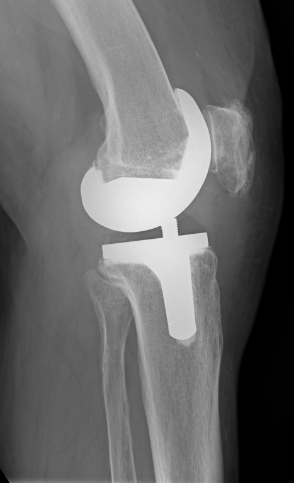

Kniegelenksersatz mit Computer-assitierte Navigation